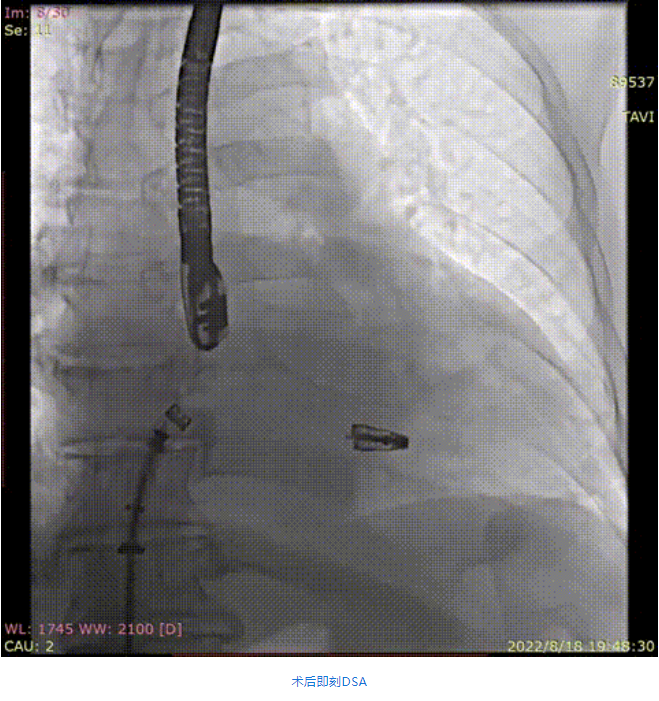

手術(shù)采用全身麻醉插管,經(jīng)股靜脈-房間隔入路,在TEE和DSA引導下完成房間隔穿刺。置入瓣膜夾系統(tǒng)后,在左房調(diào)整瓣膜夾的位置和軸向,后進入左室,在TEE引導下捕捉二尖瓣前后瓣葉,并關(guān)閉瓣膜夾。經(jīng)TEE反復確認手術(shù)效果后最終鎖定并釋放瓣膜夾。術(shù)后即刻超聲顯示瓣膜夾位置穩(wěn)定,功能良好,肺靜脈逆流和左房壓都明顯好轉(zhuǎn)。